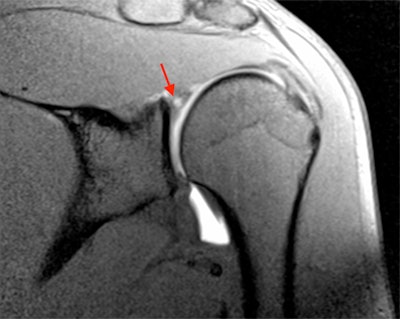

MR arthrogram image of a 27-year-old professional rugby player. There is superior labral tearing (arrow), representing a SLAP tear. Image courtesy of Dr. Andrew Grainger."Dr. Bancroft and I were keen to use this as an opportunity to compare our practices in Europe with those in America, and look at how we might alter things. The injuries seen are different, reflecting the typical sports of each country including baseball, American football, and ice hockey in the U.S. versus football and cricket in Europe," Grainger said.

Typical throwing shoulder injuries are SLAP (superior labrum anterior and posterior) tears, which may be associated with internal impingement of the shoulder seen with high-velocity movement of the upper arm. In view of the U.S.'s greater experience of these particular injuries, the U.S. radiologist's angle (given by Dr. Lynne Steinbach from the University of California, San Francisco) should highlight what to look for on a shoulder MRI.